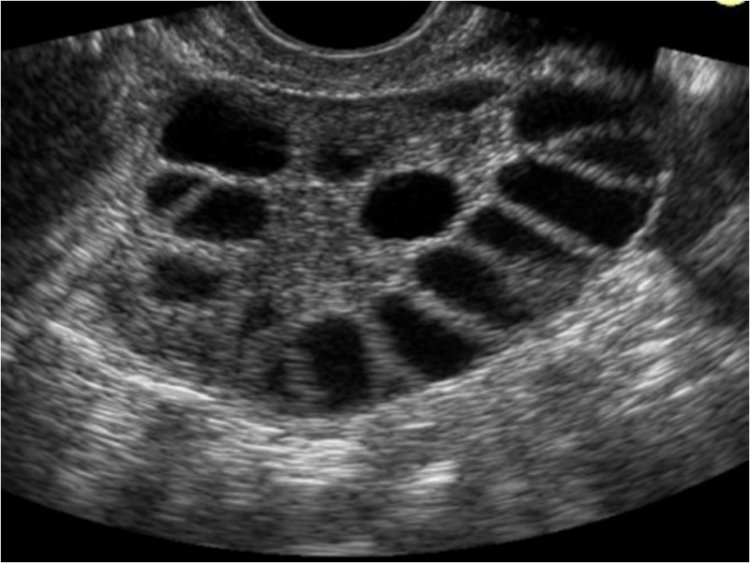

POLICITÁS OVÁRIUM SZINDRÓMA, INZULINREZISZTENCIA

„A Policisztás ovárium szindróma mellett inzulinrezisztenciám is van, valamint pajzsmirigy alulműködésem. A betegsègem, mármint a PCOS 2012-ben derült ki egy nőgyógyászati vizsgálat során. Ezután elmentem egy cukorterhelèses vizsgálatra, ahol kiderült, hogy inzulinrezisztenciám is van. Először persze arra gondoltam, mint minden normális ember, hogy miért velem törtènik ez? Aztán rájöttem, hogy ha jobban belegondolunk, ez nem is biztos, hogy rossz, ugyanis teljes èletmódváltásba kezdtem. Bejött a rendszeres sport az èletembe, a rendszeres, napi ötszöri ètkezès (persze az engedett szénhidrát-mennyiség az adott minden PCOS és IR-es betegnél is). Nekem 160g szènhidrátot kell ennem ötszöri ètkezèsben, naponta elosztva, ráadásul az sem mindegy, hogy lassú vagy gyors CH. Úgyhogy igazából ez volt a legnehezebb, hogy megszokjam ezt a fajta ètkezèst. Ráadásul időközben kiderült, hogy laktóz és tejcukor érzékeny is vagyok, úgyhogy ez sem segített az ètkezèsben. Valamint, ha bemèsz egy boltba Magyarországon, sajnos még mindig ott tartunk, hogy az egeszsègtelen ètelek sokkal olcsóbbak, mint az egészségesek.... A környezetemben eleinte furcsán fogadták, amikor 1-1 összejövetelen mondtam például egy cukros sütire, hogy én azt nem ehetem, mert nem jó a szervezetemnek. Anyukám viszont teljes mértékben segített, mindent a mai napig úgy főz vagy süt, hogy én is tudjak enni belőle. Szerencsére már egyre több ètteremben, és cukrászdában jelzik a CH tartalmát vagy, hogy van e benne valamilyen allergèn. A családom, ismerőseim persze tudják, hogy milyen betegsègem van. Haragot csak akkor èrzek, amikor 1-1 orvos azt mondja, hogy ilyen betegség nincs.... sajnos ilyen tapasztalatom is van. Nekik üzenem, hogy a pandèmia miatt nem tudtam rendszeresen edzeni járni és emiatt a diètám is volt, hogy megborult.... Nyáron pedig az egyik cisztám kipukkant, azt a fájdalmat nem kívánom senkinek sem!!! Most már szerencsére jól vagyok, és kezd helyreállni minden, de még nincs gyermekem, és a COVID miatt most minden orvosi vizsgálat nehezebben megy.”